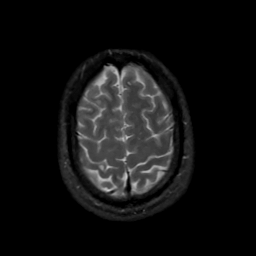

MR Study #13, May 19, 1991 -- Slice #42